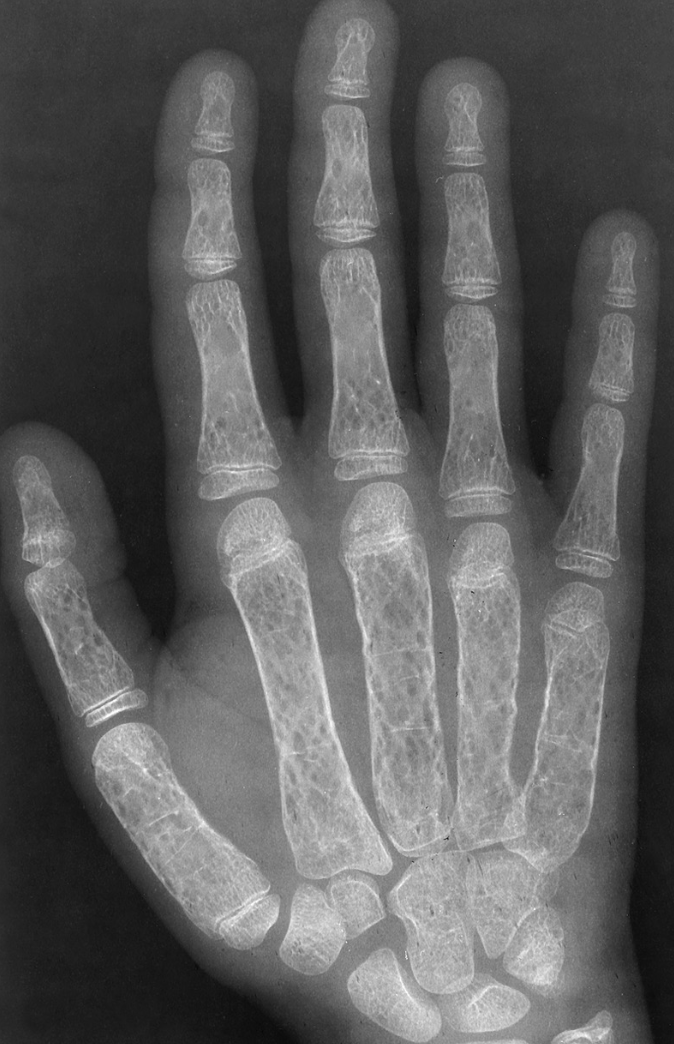

bone thinning

“Hair-on-end appearance” of thalassemia